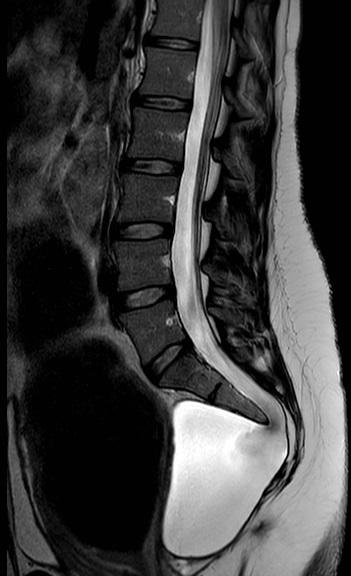

Een 29-jarige vrouw is 10 2/7 weken zwanger. Ze is misselijk en heeft steeds meer last van obstipatie, ondanks gebruik van laxantia. Eerder werden bij diagnostische laparoscopie intra-abdominaal geen afwijkingen gezien. Haar voorgeschiedenis is blanco. Er wordt een T2-gewogen MRI-scan gemaakt.